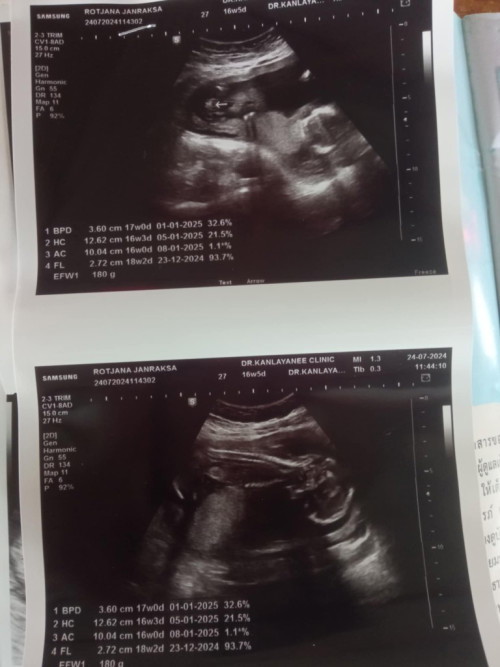

คนโต 5ขวบ3เดือน น้องสาวคนเล็กน้องนาขวัญซาวด์ตอน16+5วีค ตอนนี้19+5แล้วจ้า ❤️❤️